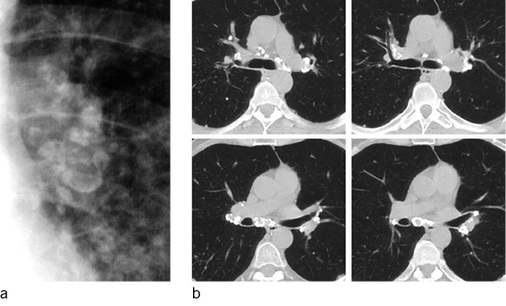

Die Schwielen sind häufig hantelförmig konfiguriert und ordnen sich bevorzugt bilateral parallel zur Thoraxwand in den Oberfeldern dorsal der Trachealebene an. Gelegentlich treten Schwielen auch im Mittel- und Unterlappen auf. Die rechte Lunge ist etwas häufiger betroffen. Im weiteren Verlauf kann es zu einer Schwielenwanderung kommen (Bohlig 1988) (  Abb. 6a ), im unkomplizierten Verlauf wandern die Schwielen in Richtung Hilus, bei begleitenden parenchymalen Narben kann auch eine Wanderung der Schwiele nach peripher mit Distraktion der Hilusstrukturen erfolgen. Die von den Hiluslymphknoten ausgehende Verschwielung kann zu Verziehungen der Gefäße und Bronchien auch mit Bronchiektasen führen. Die Bronchiallumina können eingeengt werden, in fortgeschrittenen Fällen können Bronchialverschlüsse mit angrenzenden Atelektasen besonders im Mittellappen auftreten. Differenzialdiagnostische Schwierigkeiten bestehen in der Abgrenzung von nekrobiotischen Einschmelzungen dieser Schwielen gegenüber silikotuberkulösen Kavernen und zentral einschmelzenden Lungenkarzinomen (Barboza et al. 2008; Chong et al. 2006).

Bei Arbeitern in afrikanischen Goldminen wird ein gegenüber der Normalpopulation 2,8fach erhöhtes Risiko, an Tuberkulose zu erkranken, beobachtet (Cowie 1994). Die Tuberkulose kann präexistent sein und exazerbieren, kann sich aber auch in einer vorbestehenden Silikose entwickeln. Auch bei der Infektion mit atypischen Mykobakterien kann das klinische und radiologische Bild der Silikotuberkulose auftreten. Bei morphologisch ähnlichen Befunden zwischen Silikose und Tuberkulose ist insbesondere der Vergleich mit Voruntersuchungen von eminenter Bedeutung. Finden sich neu aufgetretene Tree-in-bud-Phänomene, schnell zunehmende asymmetrisch ausgeprägte Noduli oder Konsolidierungen, insbesondere mit Einschmelzungen, ist differenzialdiagnostisch an eine floride Silikotuberkulose zu denken (Barboza et al. 2008; Martins et al. 2010) (  Abb. 6b ).